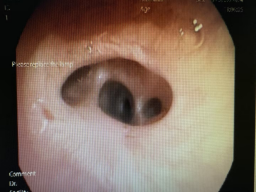

治疗前气道大约4mm宽 治疗后气道大约9mm宽

入院后,呼吸与危重症医学科主任陈波医疗团队对患者情况进行仔细检查和评估分析,认为呼吸困难原因是右中间支气管重度狭窄引起。为更好缓解患者呼吸困难症状,解决气道狭窄难题,陈波主任针对患者病情制定了在镇痛镇定+局麻下施行“球囊扩张+冷冻治疗”手术方案。经过反复研讨,充分评估患者手术风险并完善术前准备后,分别于2月7日、21日,经多次球囊扩张后再行冷冻冻融治疗,罗先生气道狭窄得以改善,气道由原来的4mm扩张到9mm,术后罗先生无不良反应,呼吸困难症状明显改善,顺利康复出院。